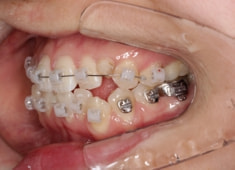

治療法:フルパッシブブラケット:T21

治療中